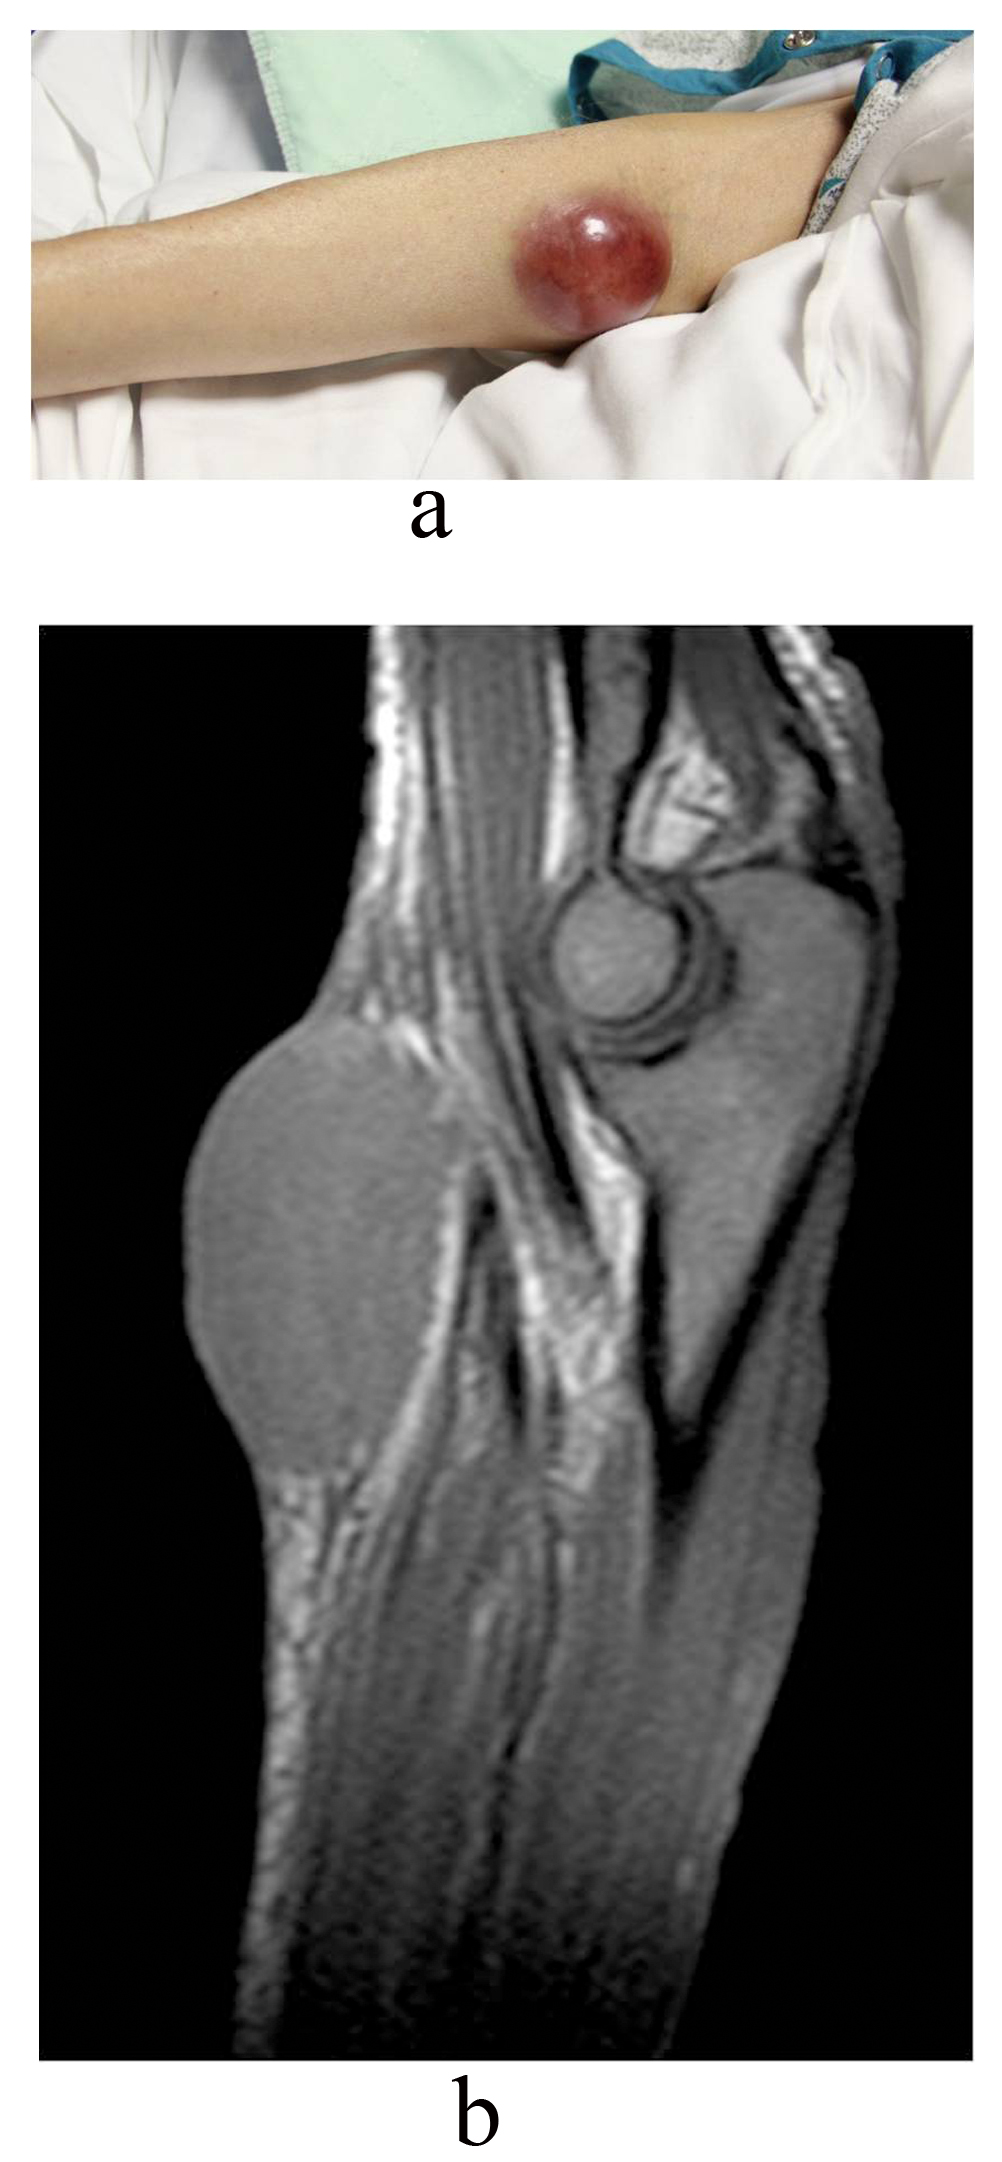

After two cycles of R-CHOP, patient developed more fatigue, right facial numbness and right ptosis, being diagnosed with idiopathic right-sided Bell’s palsy. PET scan after 4 cycles of R-CHOP demonstrated interval resolution of previously described metabolically active cervical and axillary lymphadenopathy. New metabolic activity within right inguinal lymph nodes and abdominal lymphadenopathy were found with stable splenomegaly. Patient received 1 cycle of Bendamustine (Treanda). She developed a possible “hematoma” on right medial elbow (Fig. 3a). MRI of the right upper extremity without contrast revealed the mass was not of vascular origin, likely representing a deposit of the lymphoma (Fig. 3b). During this hospitalization, patient needs blood transfusion consistently and she deteriorated quickly. Decision was made by family for comfort measures.

![]() Click for large image | Figure 3. a). Right elbow suggestive of possible “hematoma” and b) MRI of right elbow suggested deposit of lymphoma. |